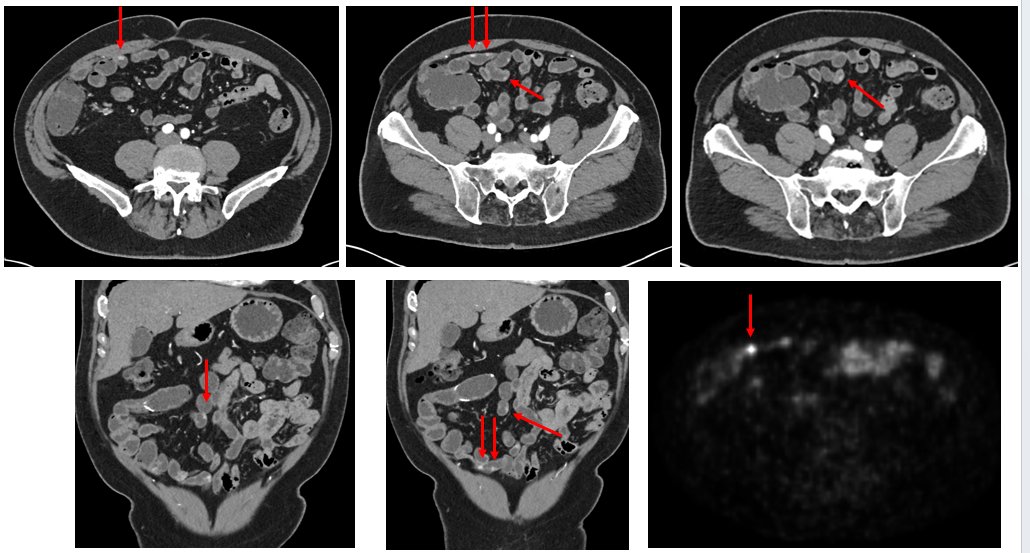

The difference quality imaging makes in the assessment of localized small ileal NETs... CT enterography... Patient who had ileal resection for multifocal G1 NETs 7 years ago (remember >50% are multifocal). Postoperative imaging showed residual multifocal NETs. On observation.